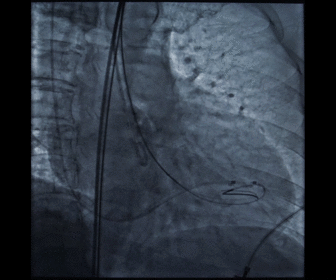

胶囊腔定位

瓣膜释放